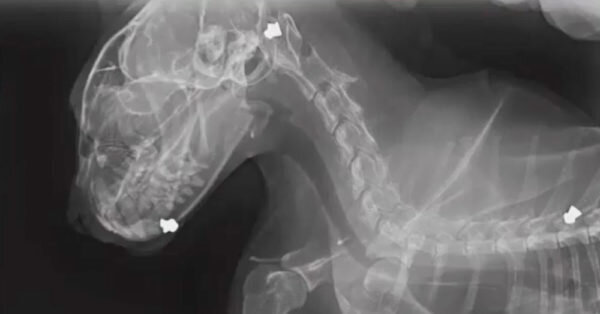

Неизвестный человек несколько раз выстрелил в несчастного кота из пневматического ружья. Но пушистик не пожелал умирать. Удивительно, что кота назвали в честь известного американского рэпера Notorious B.I.G, который также подвергался вооруженному нападению. Когда кот Бигги пропал 3 ноября, его хозяйка Николь Крандел подумала, что на него напали лисы. Но почти три недели спустя она получила звонок от ветеринара, который рассказал ей об ужасном происшествии, которое случилось с её котом. Бигги нашли живым в нескольких километрах от дома. И самое ужасное, что его нашли с несколькими ранениями от пневматического ружья. «Дробь попала в его голову, щеки, шею, челюсть и спину», - рассказала Николь. Николь не могла поверить, что её кот остался жив после такого происшествия. Все пули из тела пушистика удалили, и ветеринар сделал все необходимые процедуры. Николь много ухаживала за своим питомцем и радовалась, что несмотря на такое ранение, Бигги довольно быстро поправлялся. Но она переживала о

«Дробь попала в его голову, щеки, шею, челюсть и спину», - рассказала Николь.

«Ветеринар сказал, что в Бигги, очевидно, стреляли сверху вниз, держа ружье почти возле головы. Получается, что кто-то ранил кота нарочно», - говорит Николь.